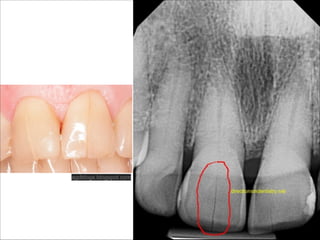

Visual  examination

Radiographs

Transillumination

www.mahwahsmile.com

http://www.endodovgan.com/Endoinfo_Cracked_Fractured.htm